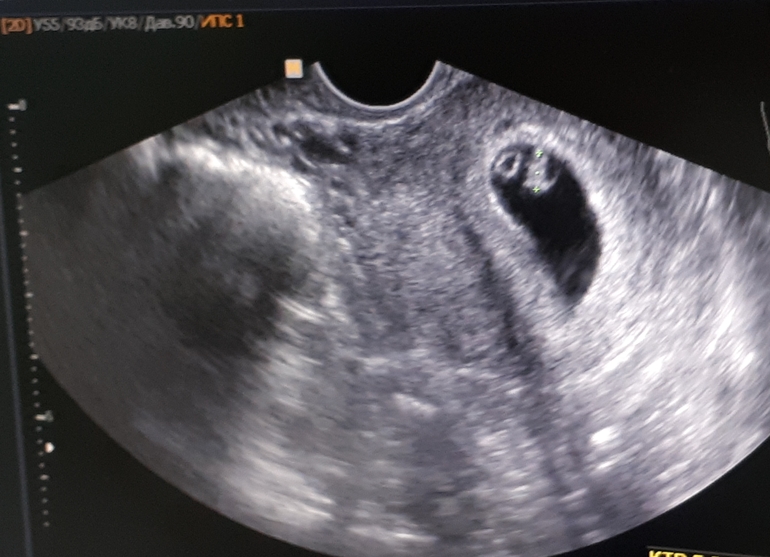

УЗИ на 6нед 3д

Сходила сегодня на УЗИ,сказали все хорошо сердечко бьется💓И на той недели ходила в 5,сердечко еще не билось☺😍Вот наше чудо😍так долго ждали мы этого малыша🙏Наш подарок на новый год🤰🎉Девочки всем вам желаю такого счастья😚😚😚Берегите себя🙏🙏🙏